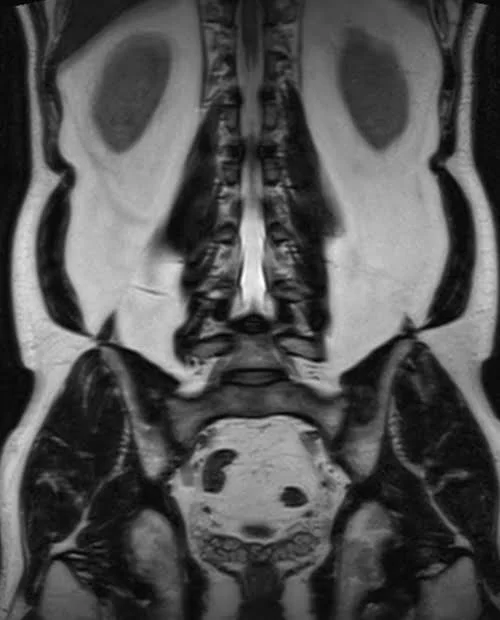

l plexus mri SPACE 3D coronal images